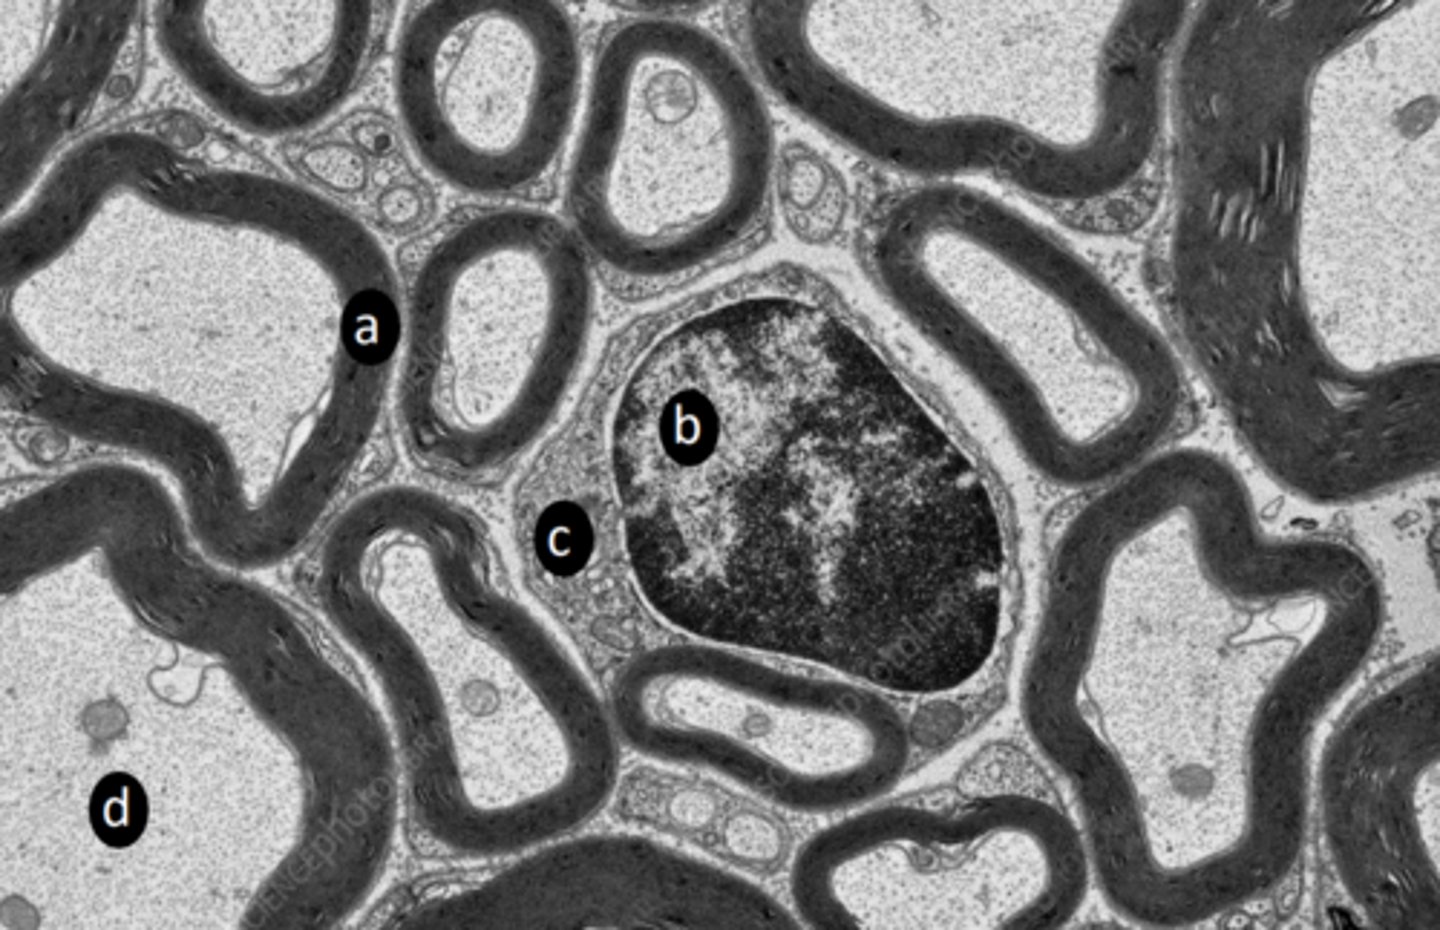

axon

a: structure

<p>a: structure</p>

neurofilament

neurotubule

b: structure

<p>b: structure</p>

Schwann cell cytoplasm

red: structures

<p>red: structures</p>